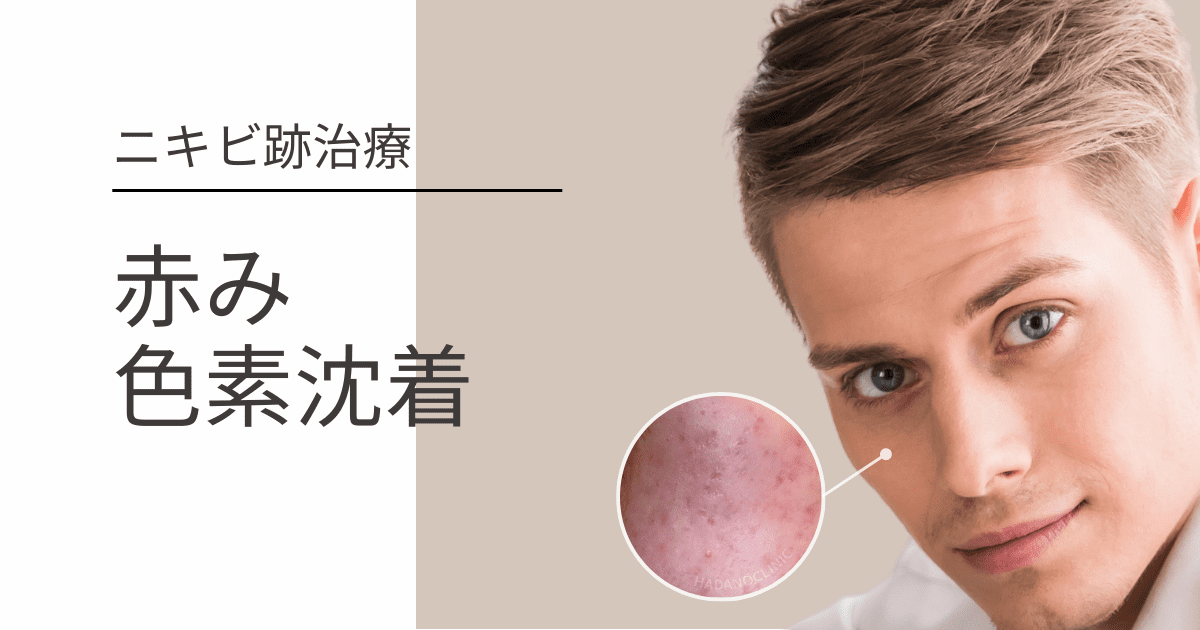

ニキビ跡の色素沈着によるシミについてはなふさ皮膚科・美容皮膚科 関東・関西・東海・九州エリアに16院。

赤み・色素沈着症例紹介ニキビ跡のクレーター・毛穴でお悩みの方へ「花房式ニキビ跡治療」。

ニキビ跡の色素沈着はレーザー治療で消すニキビ治療・ニキビ跡治療の東京イセアクリニック。